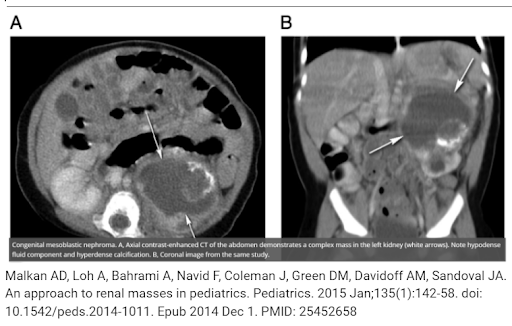

What is the most common benign kidney tumor in neonates?

Ans:💥 Mesoblastic Nephroma

📌Most common neonatal kidney mass

📌M>F

📌polyhydramnios, hydrops & preterm birth

📌US: the “ring” sign- concentric hyper & hypoechoic rims surrounding tumor

📌Path: interlacing fibro/myofibroblastic cell bundles interspersed with collagen & vessels